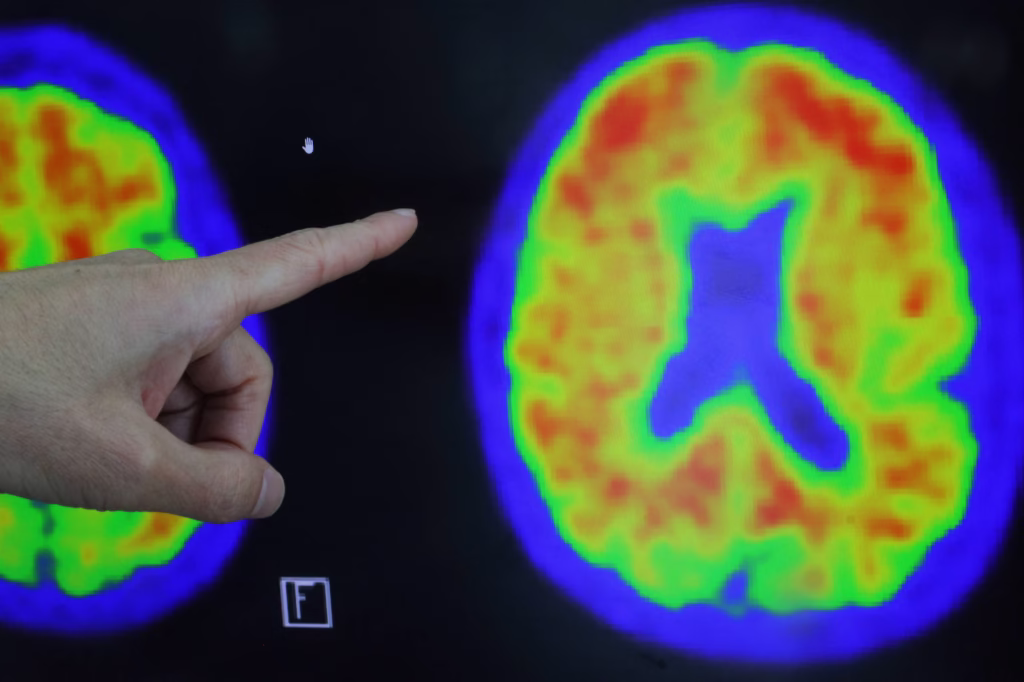

O Kisunla (donanemabe), fabricado pela farmacêutica Eli Lilly, é um anticorpo monoclonal que se liga ‘a proteína beta-amiloide. Na doença de Alzheimer, aglomerados de proteína beta-amiloide formam placas no cérebro e o medicamento atua ligando-se a esses aglomerados e reduzindo-os, prometendo um retardamento da progressão da doença.